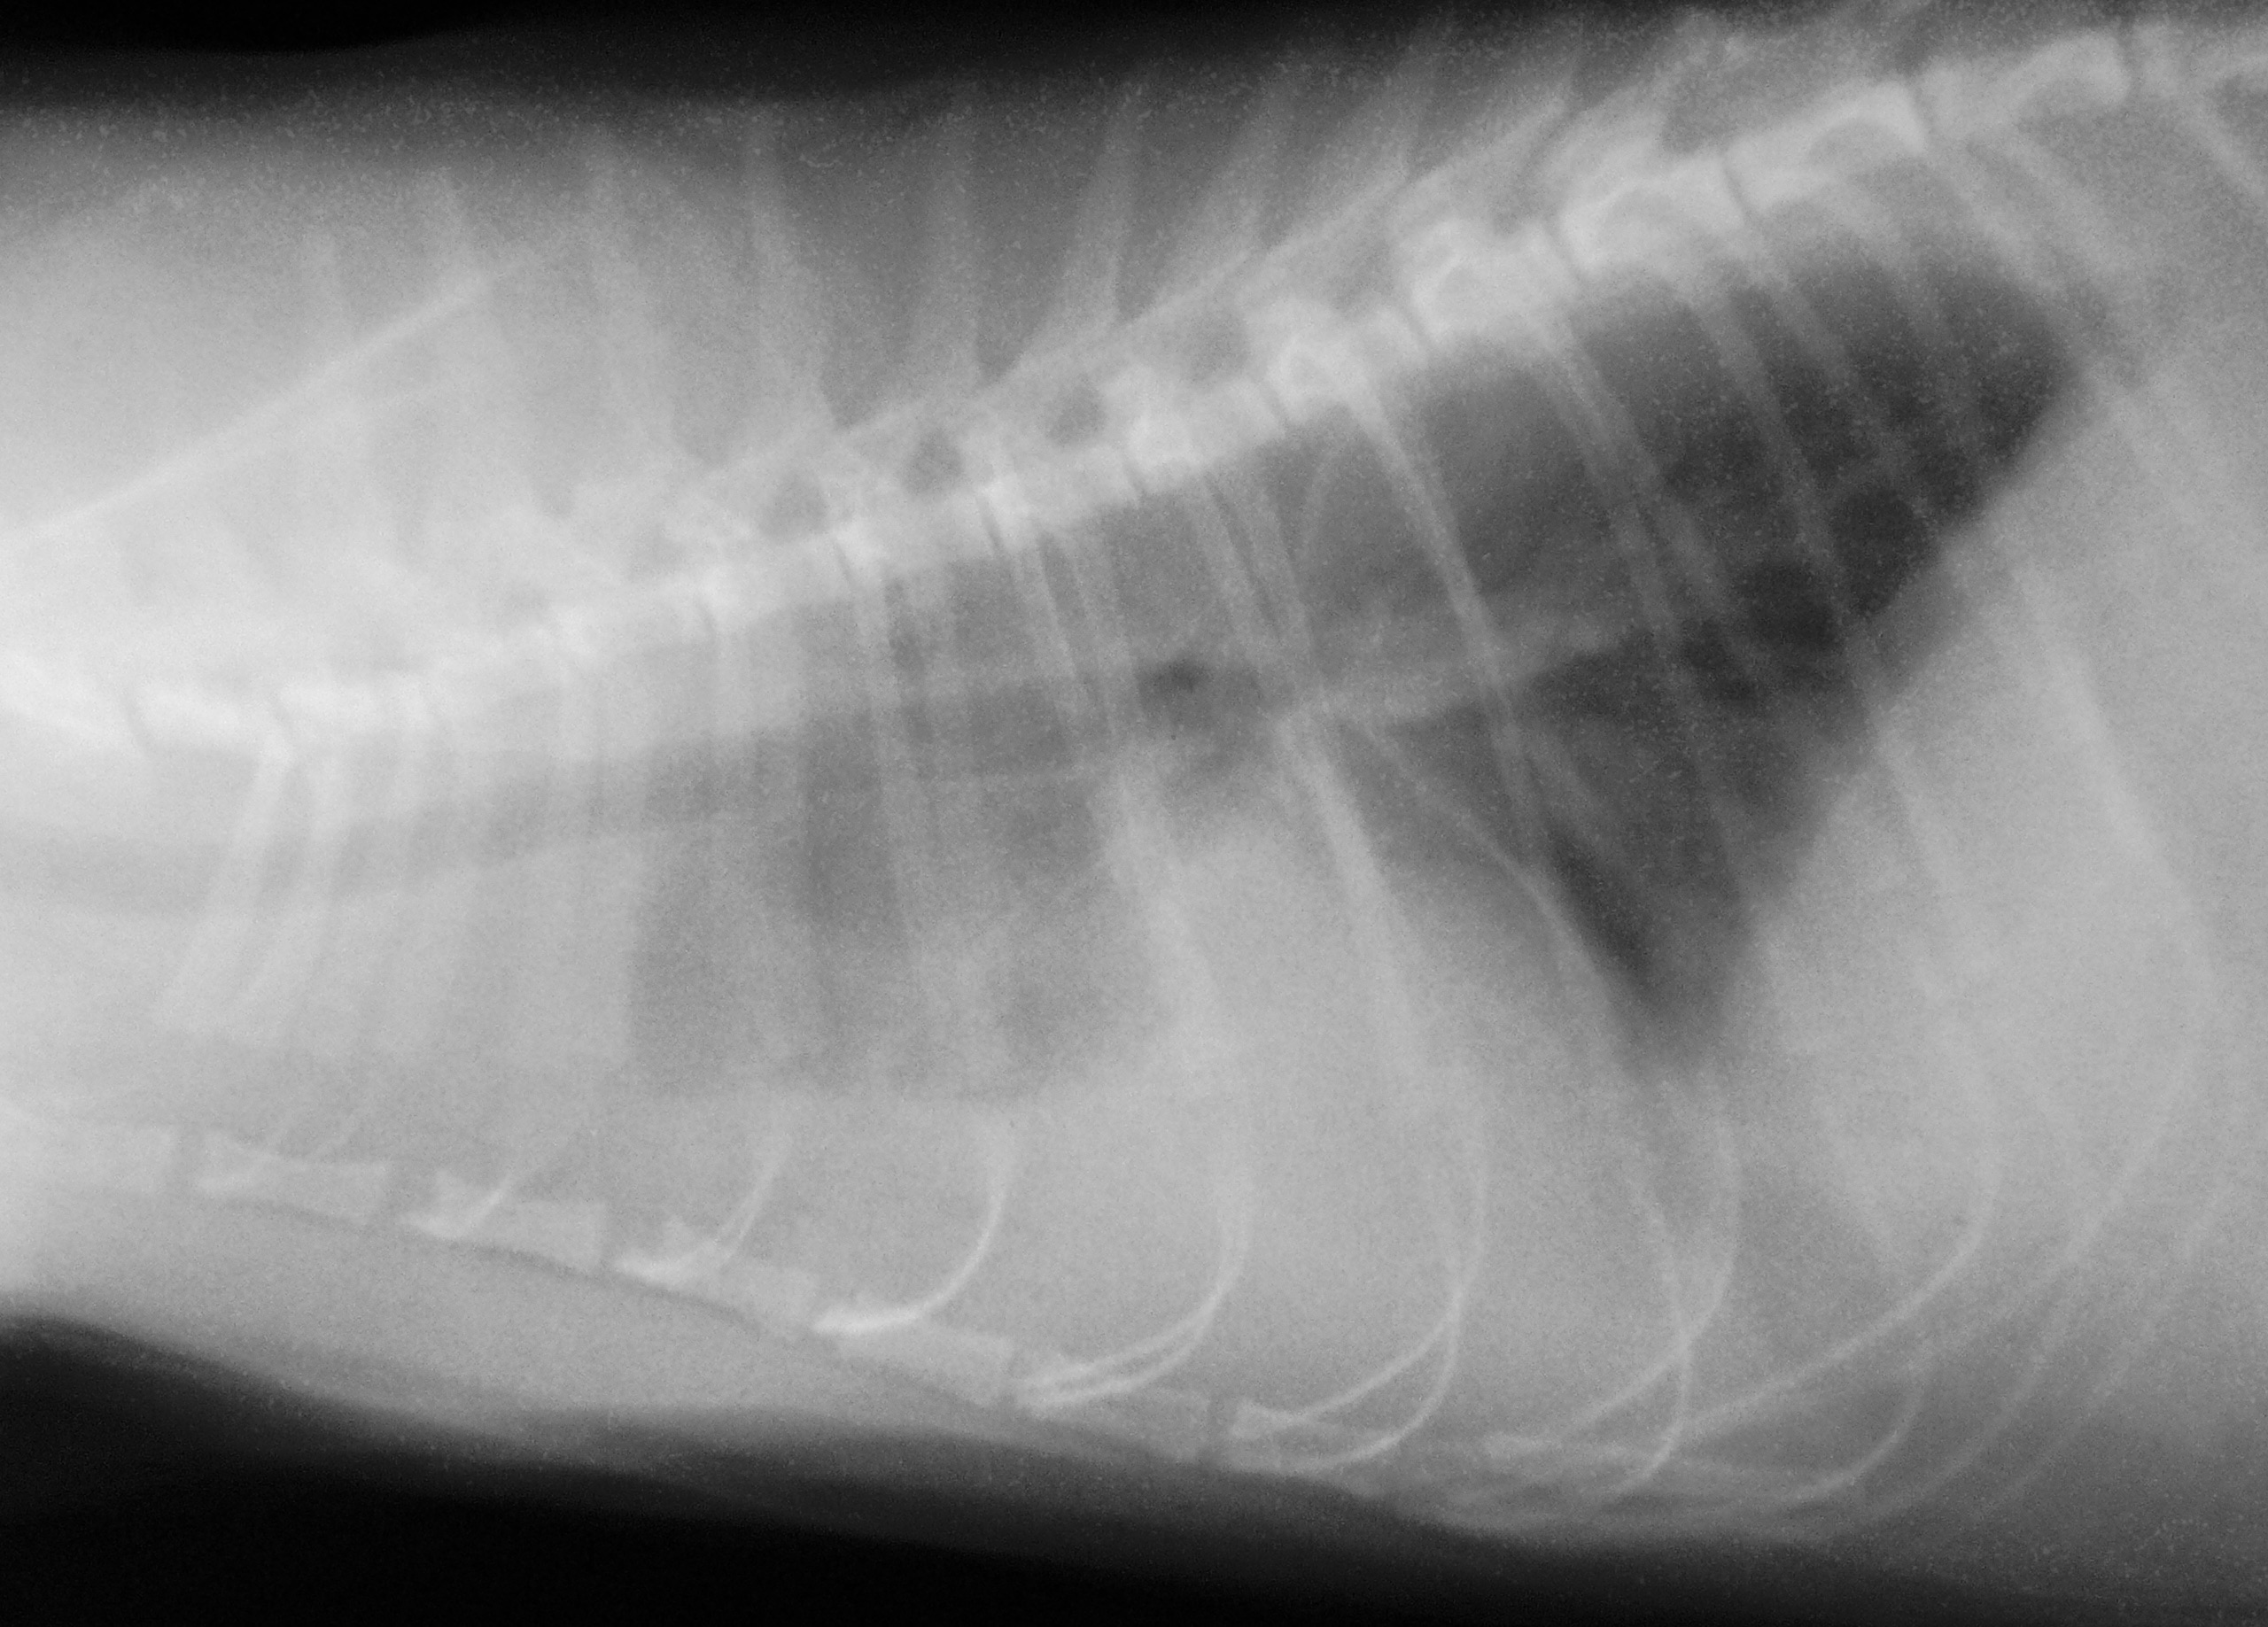

Photo de gauche : cette radio ancienne montre un

épanchement pleural, qui masque une grande partie du cœur et toute la partie crâniale du thorax (à gauche sur la radio), chez un chat de 1 an présentant une forme humide de PIF, avec également une ascite. Par comparaison, ci-dessus, une image normale du thorax chez un chat de 8 ans, également atteint de PIF, mais avec « seulement » une ascite modérée.